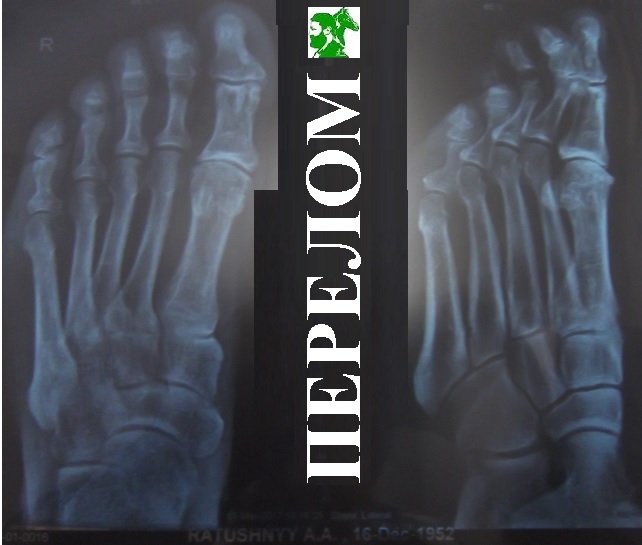

Перелом!

Такой весёлый перелом!

Запнулся я, ломая кость,

Совсем малюсенькую ость,